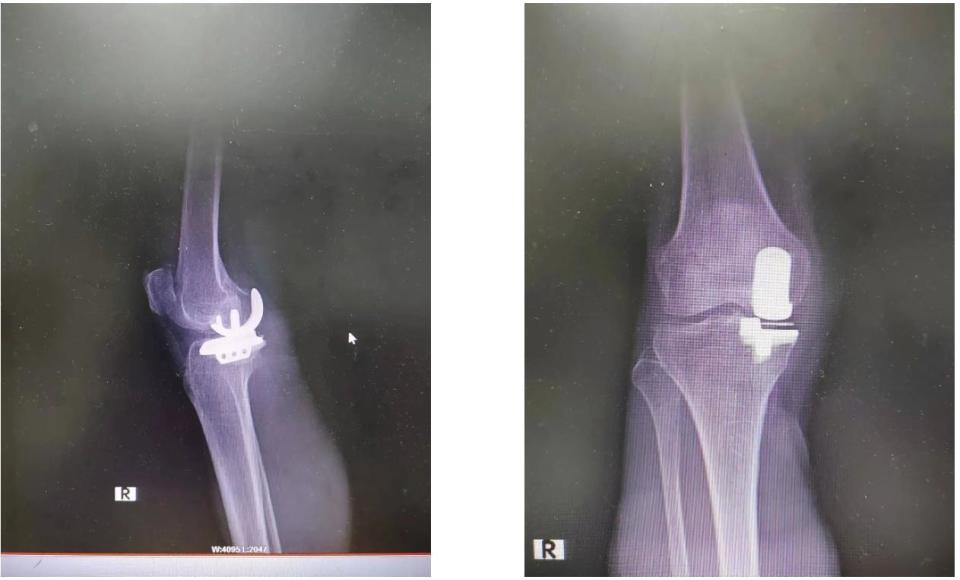

60岁女性,右膝关节骨性关节炎,单髁关节置换术. - 好大夫在线

图片尺寸4032x3024